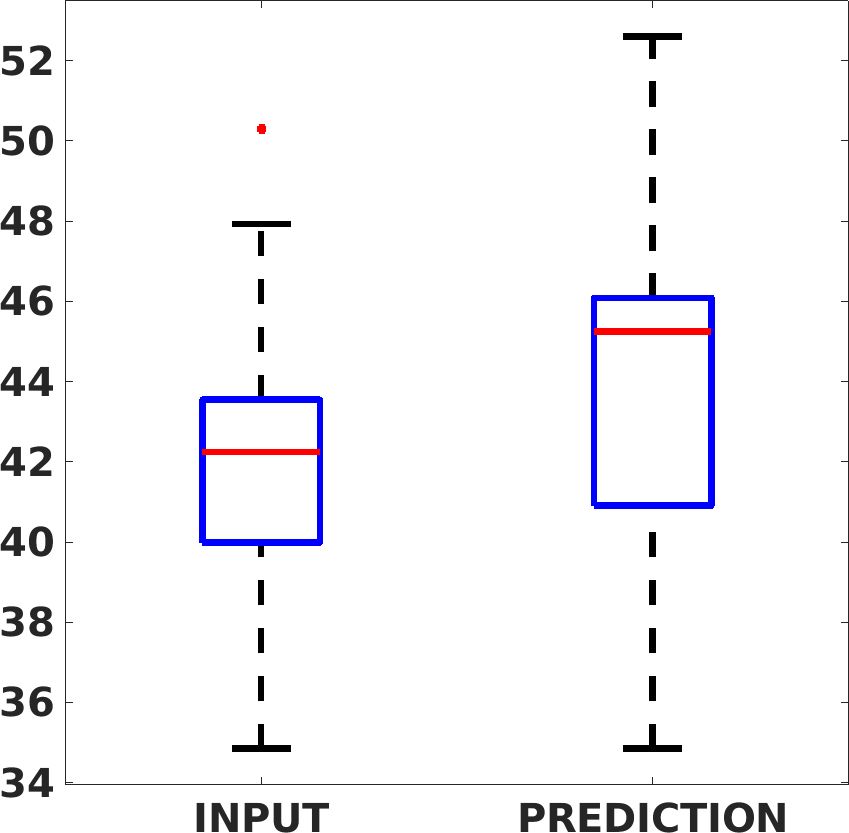

Fig. 17 (left) shows the box plot of the quantitative metrics, comparing the target images with the prediction and the Cubic convolution, respectively. The PSNR metric is computed on a data set of 200 images, belonging to the same district, and with the same up-sampling factor. Analysing the obstetric anatomical district and concerning the corresponding raw images (Fig. 7 (a, left)), the denoising allows the network to significantly improve the results of the up-sampling and the prediction. In particular, comparing the target images with the predicted images, the median PSNR value of obstetric 2X denoised images is 51.8, compared to the median PSNR value of obstetric 2X raw images which is 36.9.

Fig. 17 (right) shows the histogram of the absolute value of the error with respect to the target, of the prediction and Cubic convolution respectively. This result shows that our framework increase of and (2X and 4X, respectively) the number of pixels where the prediction error is lower than 5, which is very similar to the target when visually analysing the images, and improved with respect to the learning framework applied to raw images. According to Fig. 18, our method improves the accuracy of Cubic convolution. For example, the SSIM increases of on cardiac 2X and the MAE increases of on abdominal 4X.